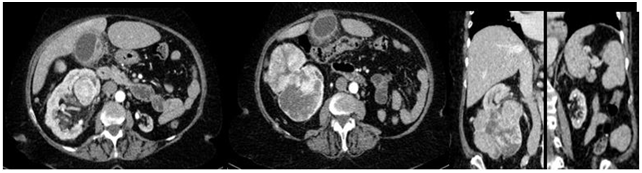

The specimen weighed 640 grams and anatomopathological analysis with immunohistochemistry confirmed renal cell carcinoma of the chromophobe type, with the renal capsule free of neoplastic involvement and the absence of invasion of Gerota’s fascia. Postoperative follow-up was performed through laboratory analysis (Figure 3), physical examination, and imaging examination (Figure 4) within 90 days of surgery without evidence of relapse of the disease and the patient maintaining preserved global renal function.

Figure 4 Magnetic resonance imaging of the abdomen with contrast without evidence of recurrence with vicarious right kidney postoperative follow-up.